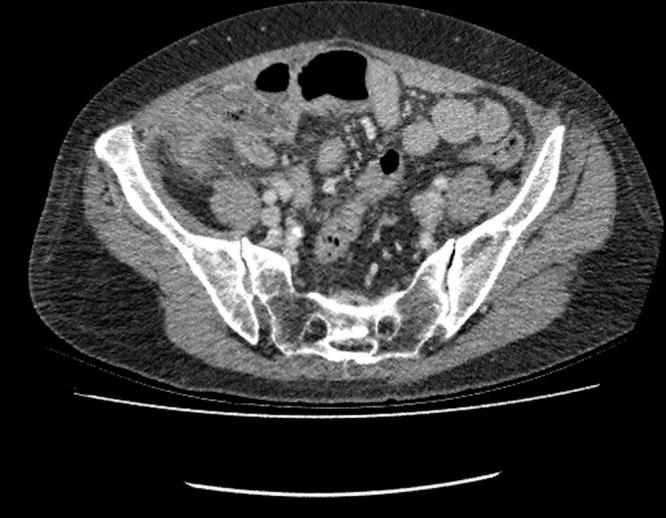

Gastric cancer is a common malignancy with high recurrence rates following surgical resection. A common site of disease recurrence is the peritoneum. We report the case of a 73-year-old female who had previously undergone a total gastrectomy for gastric cancer who presented acutely with features classical of acute appendicitis and underwent open appendectomy. Histological analysis showed metastasis of gastric cancer with clear resection margins. The patient recovered fully and has remained disease-free for 14 months following presentation. Peritoneal metastasis is associated with difficulty in treatment and poor prognosis. The unplanned excision of this patient's peritoneal metastasis has yielded a favourable clinical outcome in a difficult clinical situation.

胃癌是一种常见的恶性肿瘤,手术切除后复发率很高。疾病复发的常见部位是腹膜。我们报告一例73岁女性病例,该患者此前因胃癌接受了全胃切除术,现因出现典型的急性阑尾炎症状而急症就诊,并接受了开腹阑尾切除术。组织学分析显示胃癌转移,切缘清晰。患者已完全康复,就诊后14个月无疾病复发。腹膜转移与治疗困难和预后不良相关。该患者腹膜转移灶的意外切除在困难的临床情况下取得了良好的临床效果。